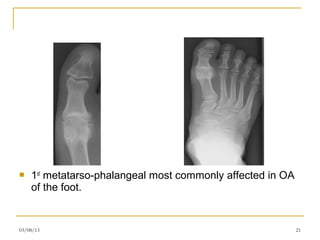

   1st metatarso-phalangeal most commonly affected in OA

of the foot.

1st metatarso-phalangeal most commonly affected in OA of the foot. 03/08/13 21